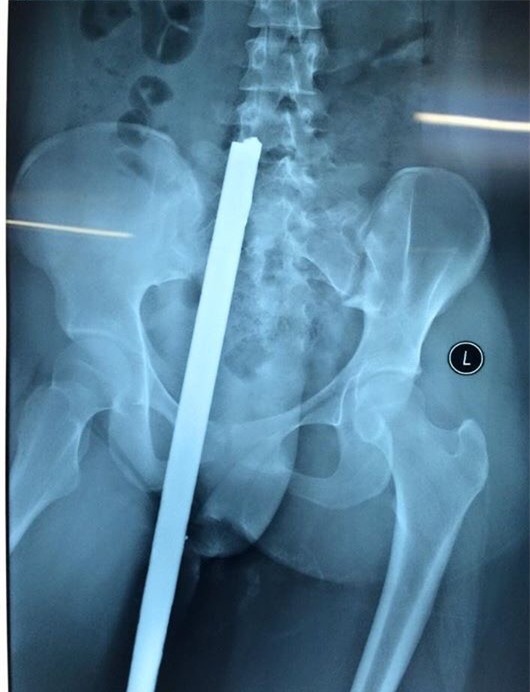

Nữ sinh 16 tuổi bị thanh sắt đâm xuyên người

Trên đường đi học về, một nữ sinh 16 tuổi ở Bắc Ninh đã bất ngờ bị thanh sắt dài từ xe 3 bánh chở vật liệu xây dựng đâm phải. Cú đâm mạnh đã khiến thanh sắt dài cắm xuyên từ mông đến thắt lưng thiếu nữ. Xem chi tiết tại đây